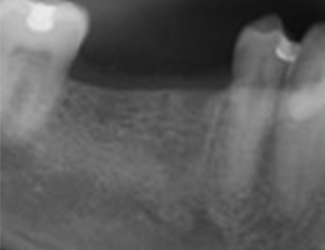

45-årig man som för fem månader sedan genomgick extraktion av tand 45 och 46.

Fem månader senare visades god läkning av såväl ben som mjukvävnad.

1. Utgångsläge före implantatinstallation.